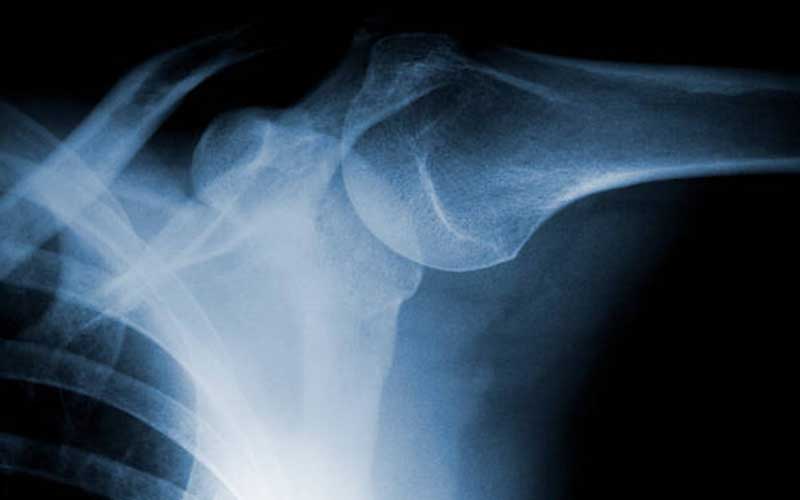

Omuz Kireçlenmesi Nasıl Teşhis Edilir?

Teşhis sürecinde öncelikle hastanın hikayesi dinlenir ve fizik muayene yapılır. Ardından kireçlenmenin derecesini belirlemek için radyolojik incelemeler (röntgen, MR) kullanılır. Doktor; hastanın yaşı, şikayet süresi, mesleği ve fiziksel aktivite düzeyine göre tedavi planını şekillendirir.